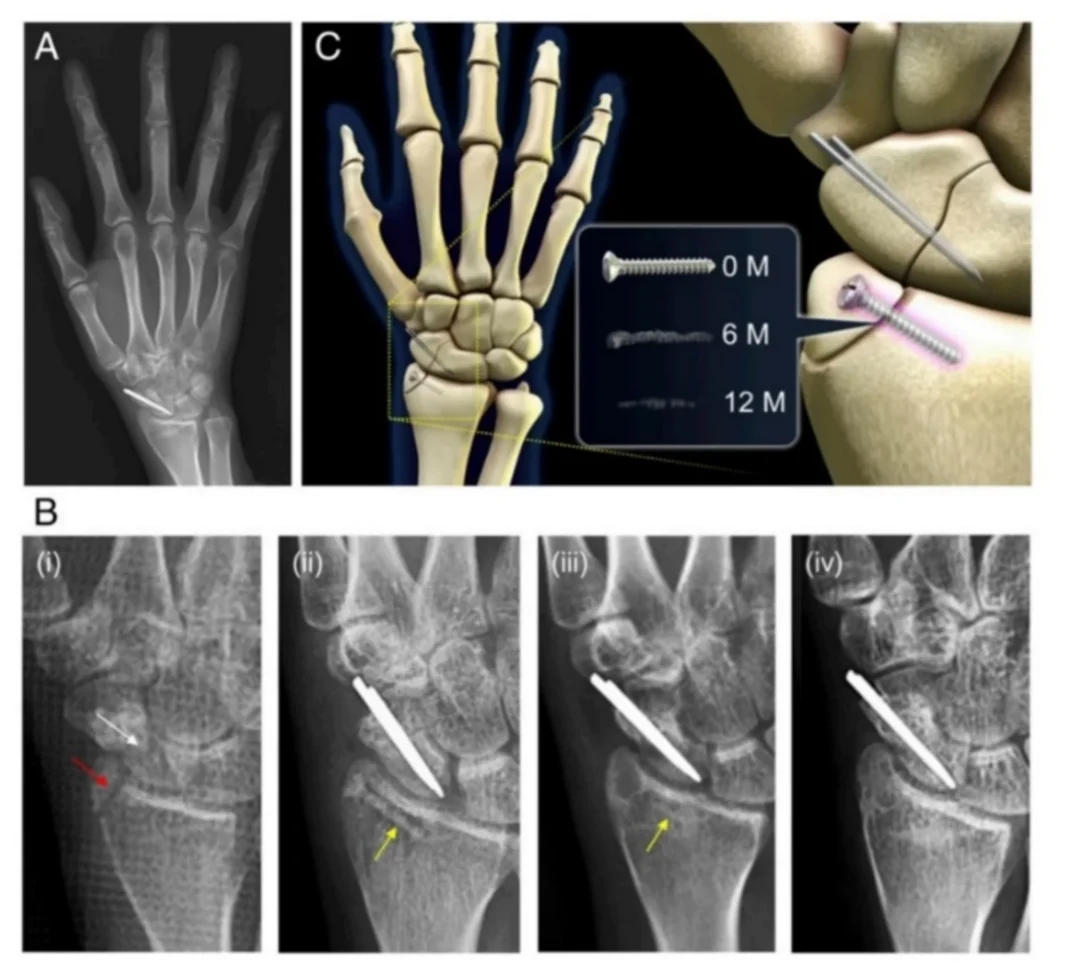

Τα δείγματα εμφάνισαν χαμηλή τοξικότητα, βιοαποδομησιμότητα και ενδείξεις ότι είναι αξιόπιστα για την ανάπτυξη των οστών. Η μελέτη δημοσιεύτηκε στο Biomedical Materials. Για να επουλωθούν τα σοβαρά κατάγματα, τοποθετούνται εμφυτεύματα που διευκολύνουν την αναγέννηση των ιστών στη θέση του οστού που λείπει. Στην ουσία, χρησιμεύουν ως μήτρα στην οποία σχηματίζεται σταδιακά νέο οστό. Ιδανικά, τα εμφυτεύματα θα πρέπει να έχουν διαλυθεί μέχρι να ολοκληρωθεί η δουλειά τους. Η νέα μελέτη περιγράφει λεπτομερώς τις δοκιμές ενός κράματος σιδήρου-πυριτίου για την κατασκευή τέτοιων εμφυτευμάτων.

Για να λειτουργήσουν σωστά, τα υλικά για εμφυτεύματα θα πρέπει να πληρούν ορισμένα κριτήρια. Πρέπει να είναι στιβαρά, όπως τα οστά, και πορώδη—έτσι ώστε να παρέχουν χώρο για την ανάπτυξη των ιστών. Πρέπει επίσης να είναι βιοσυμβατά και βιοαποδομήσιμα. Δηλαδή, το εμφύτευμα θα πρέπει να γίνεται αποδεκτό από τον οργανισμό και να αποσυντίθεται φυσικά με την πάροδο του χρόνου, αλλά όχι πολύ γρήγορα, ώστε το οστό να έχει αρκετό χρόνο προκειμένου να αναπτυχθεί. Επίσης, η αποδόμηση του υλικού δεν πρέπει να παράγει τοξικές ενώσεις. “Χρησιμοποιούνται συχνά κράματα σιδήρου, επειδή αυτό το μέταλλο είναι φιλικό προς το σώμα και διασπάται με τον σωστό σχεδόν ρυθμό, αλλά είναι επίσης πολύ μαλακό εάν χρησιμοποιείται χωρίς πρόσθετα. Η ομάδα μας είχε εμπειρία με κράματα σιδήρου και πυριτίου στο παρελθόν , και σκεφτήκαμε ότι πρέπει να τα δοκιμάσουμε σε αυτό το πλαίσιο, επειδή το πυρίτιο είναι επίσης γνωστό ότι είναι εξαιρετικά βιοσυμβατό, μη τοξικό, απορροφάται και εκκρίνεται εύκολα», δήλωσε η επικεφαλής συγγραφέας της μελέτης, Junior Research Scientist Julia Bondareva από το Skoltech.

“Χρησιμοποιήσαμε έναν τρισδιάστατο εκτυπωτή για να παράγουμε δείγματα πορώδους σιδήρου-σιλικόνης από σκόνη. Τα δείγματα είχαν αυθαίρετο σχεδιασμό κατάλληλο για τις προβλεπόμενες δοκιμές των μηχανικών και βιολογικών ιδιοτήτων τους. Σκοπεύουμε να παράγουμε εμφυτεύματα ανατομικού σχήματος για δοκιμές σε ζώα”, εξήγησε ο Stanislav Evlashin, κύριος ερευνητής. Η ομάδα ερεύνησε τις μηχανικές ιδιότητες του κράματος για να καθορίσει πόσο καλά τα εμφυτεύματα θα άντεχαν τη συμπίεση και την επέκταση, σε σύγκριση με τον καθαρό σίδηρο και τα άλλα κράματα του μετάλλου που χρησιμοποιούνται ήδη για το σκοπό αυτό. Τα δείγματα πυριτίου-σιδηρού αποδείχθηκαν ανώτερα από εκείνα που κατασκευάζονται από καθαρό σίδηρο και τα άλλα κράματά του. «Δείξαμε επίσης ότι τα εμφυτεύματα θα αποσυντεθούν όπως αναμενόταν με την πάροδο του χρόνου», πρόσθεσε η Bondareva. «Χαρτογραφήσαμε επίσης τη στοιχειακή σύνθεση των δειγμάτων», σημείωσε ο Evlashin. “Η σκόνη που χρησιμοποιούμε για την εκτύπωση περιέχει σίδηρο και πυρίτιο σε μια ορισμένη αναλογία, και υπάρχει πάντα κάποια οξείδωση όταν εκτυπώνουμε σε υψηλή θερμοκρασία με λέιζερ. Έτσι, προκειμένου να βεβαιωθούμε ότι οι μηχανικές ιδιότητες είναι λίγο πολύ οι ίδιες σε οποιαδήποτε σημείο στο δείγμα, έπρεπε να επιβεβαιώσουμε ότι η αναλογία μεταξύ των δύο συστατικών στοιχείων -και του οξυγόνου επίσης- ήταν σωστή και ομοιόμορφα κατανεμημένη σε όλο το δείγμα.”

Μετά τη σύνθεση του υλικού και τις μηχανικές δοκιμές στο Skoltech, τα δείγματα έφτασαν στο Πανεπιστήμιο Sechenov, όπου πραγματοποιήθηκαν περαιτέρω δοκιμές με ζωντανά κύτταρα σε φυσιολογικό διάλυμα. Η μικροσκοπία έδειξε ότι περίπου το 70% των κυττάρων παρέμειναν ζωντανά, υποδηλώνοντας χαμηλή τοξικότητα λόγω του σχηματισμού υδροξειδίου και χλωρίου σιδήρου κατά την αποικοδόμηση του δείγματος. Είναι σημαντικό ότι παρατηρήθηκε εναπόθεση φωσφορικού ασβεστίου στα δείγματα—δηλαδή, ο οστικός ιστός άρχισε να σχηματίζεται στο «εμφύτευμα».